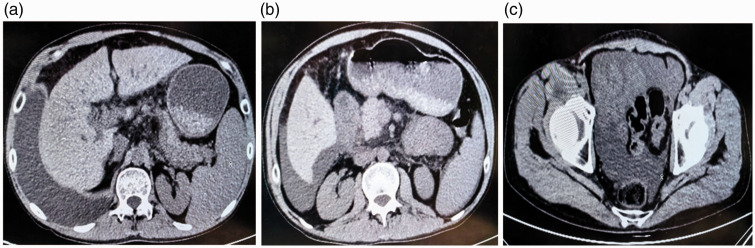

本病例报告详细介绍了肝硬化患者乳糜胸膜和腹膜积液的处理。患者有28年未经治疗的乙肝病史,到高海拔地区旅行后出现呼吸困难和咳嗽。影像学和实验室检查证实有乳糜积液。治疗包括胸腔穿刺、穿刺、抗生素、生长抑素类似物和支持性护理。患者病情明显好转,出院后随访无复发。本病例强调了肝硬化乳糜积液的早期诊断和保守治疗的重要性,强调了生长抑素类似物在减少积液形成和促进淋巴愈合方面的潜在作用。

This case report details the management of a patient with cirrhosis who developed chylous pleural and peritoneal effusions. The patient, with a 28-year history of untreated hepatitis B, presented with dyspnea and cough after traveling to a high-altitude area. Imaging and laboratory tests confirmed the presence of chylous effusions. Treatment included thoracentesis, paracentesis, antibiotics, somatostatin analogs, and supportive care. The patient showed significant improvement and was discharged with no recurrence at follow-up. This case highlights the importance of early diagnosis and conservative management of chylous effusions in cirrhosis, emphasizing the potential role of somatostatin analogs in reducing effusion formation and promoting lymphatic healing.